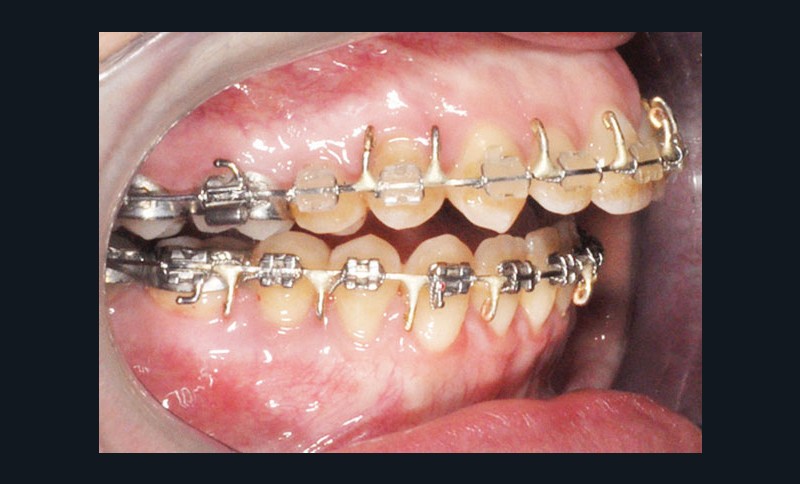

Étapes de traitement

(fig. 2, 3, 4, 5 et 6)

– préparation orthodontique avec recul molaire mandibulaire sur miniplaques à l’aide de corticotomies alvéolaires

Distalisation molaire mandibulaire par corticotomies associées aux miniplaques (fig. 7)

Avantages

Le recul molaire a apporté l’espace nécessaire à la correction de l’encombrement avec en plus un léger recul incisif qui a permis de positionner de façon idéale l’incisive dans la symphyse. Une distalisation des secteurs latéraux de 3 mm à droite et 2 mm à gauche permettant aussi de symétriser les relations molaires a donc été obtenue en…